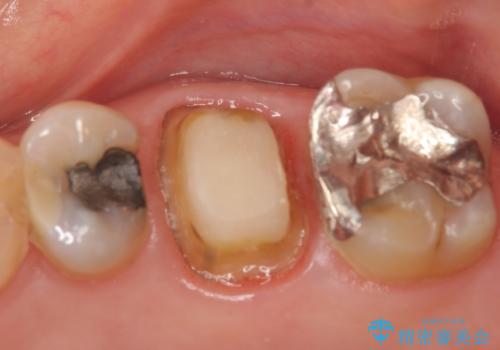

- 左上の奥歯にできものが出来てから口臭が気になるようになったので診て欲しいといらっしゃった方の症例です。

左上のできものは左上6の根尖病変が原因のフィステル(膿の出口)であったため、再根管治療を行いました。

フィステルの消失を確認後、オールセラミッククラウンによる補綴を行いました。